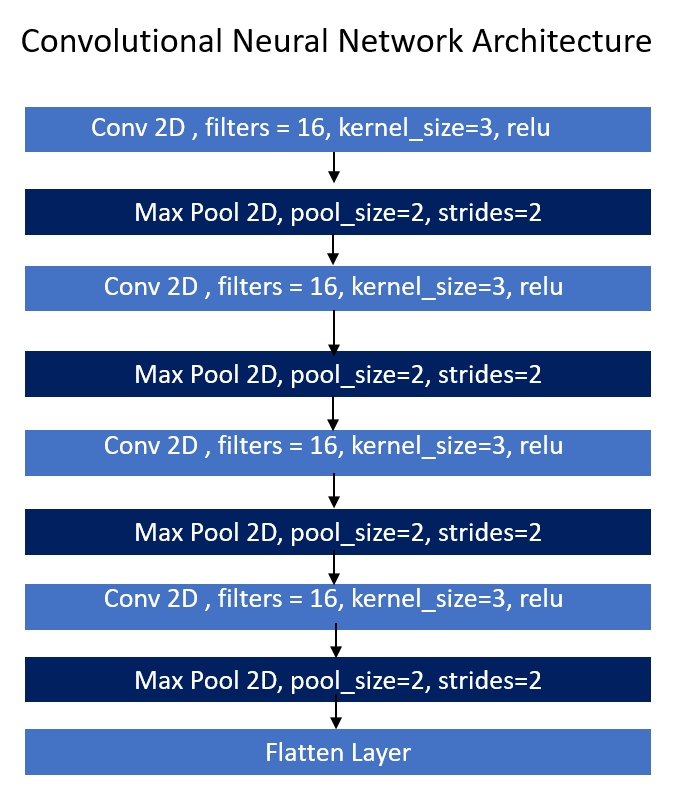

Now lets move forward to create our Convolutional neural network. I have create a new function in the same class of brain_tumor as you can see below.

As you can see in the image alongside, there are 9 layers i.e Conv2D, Max Pool 2D followed by Flatten layer at the last. The first layer is of conv 2D whereas the second layer is Max pool 2D layer. This is the alternate sequence i followed till the end. The output of conv2D is given to max pool 2 D layer which will give to forward conv2D and respectively.

The calculation between the image pixel and kernel values is known as convolve. New image extracted by convolution is always small because after some important feature extraction the pixels are reduced in the new image therefore the new image is always small compare to original image. But this image include more pixels of same information (color, objects) as there are more pixels in the convolved image then for training this image there’s requirement of high processing power as well as cost. To reduce this requirement we can reduce the pixel of the same information and merge them into one pixel. This can be achieved by Pooling. There are three types of pooling 1) Max Pooling 2) Average Pooling 3) Sum Pooling. We use Max pooling in many of the cases but it depends on requirements. Below is an example of Max pooling.

There is a layer of activation function ‘relu’. This relu activation will give only positive value to next convolutional layer i.e if first convolutional layer transfers negative value to next convolutional layer then relu will send only positive value and will convert the negative value to zero. Because there cannot be negative prediction. This layers are in 2D and machine learning model not understand higher dimensional inputs there we have to flatten these layers value and convert this into 1D and then this flatten values will acts as a input to neural network i.e is to send flatten values to Fully connected layer.